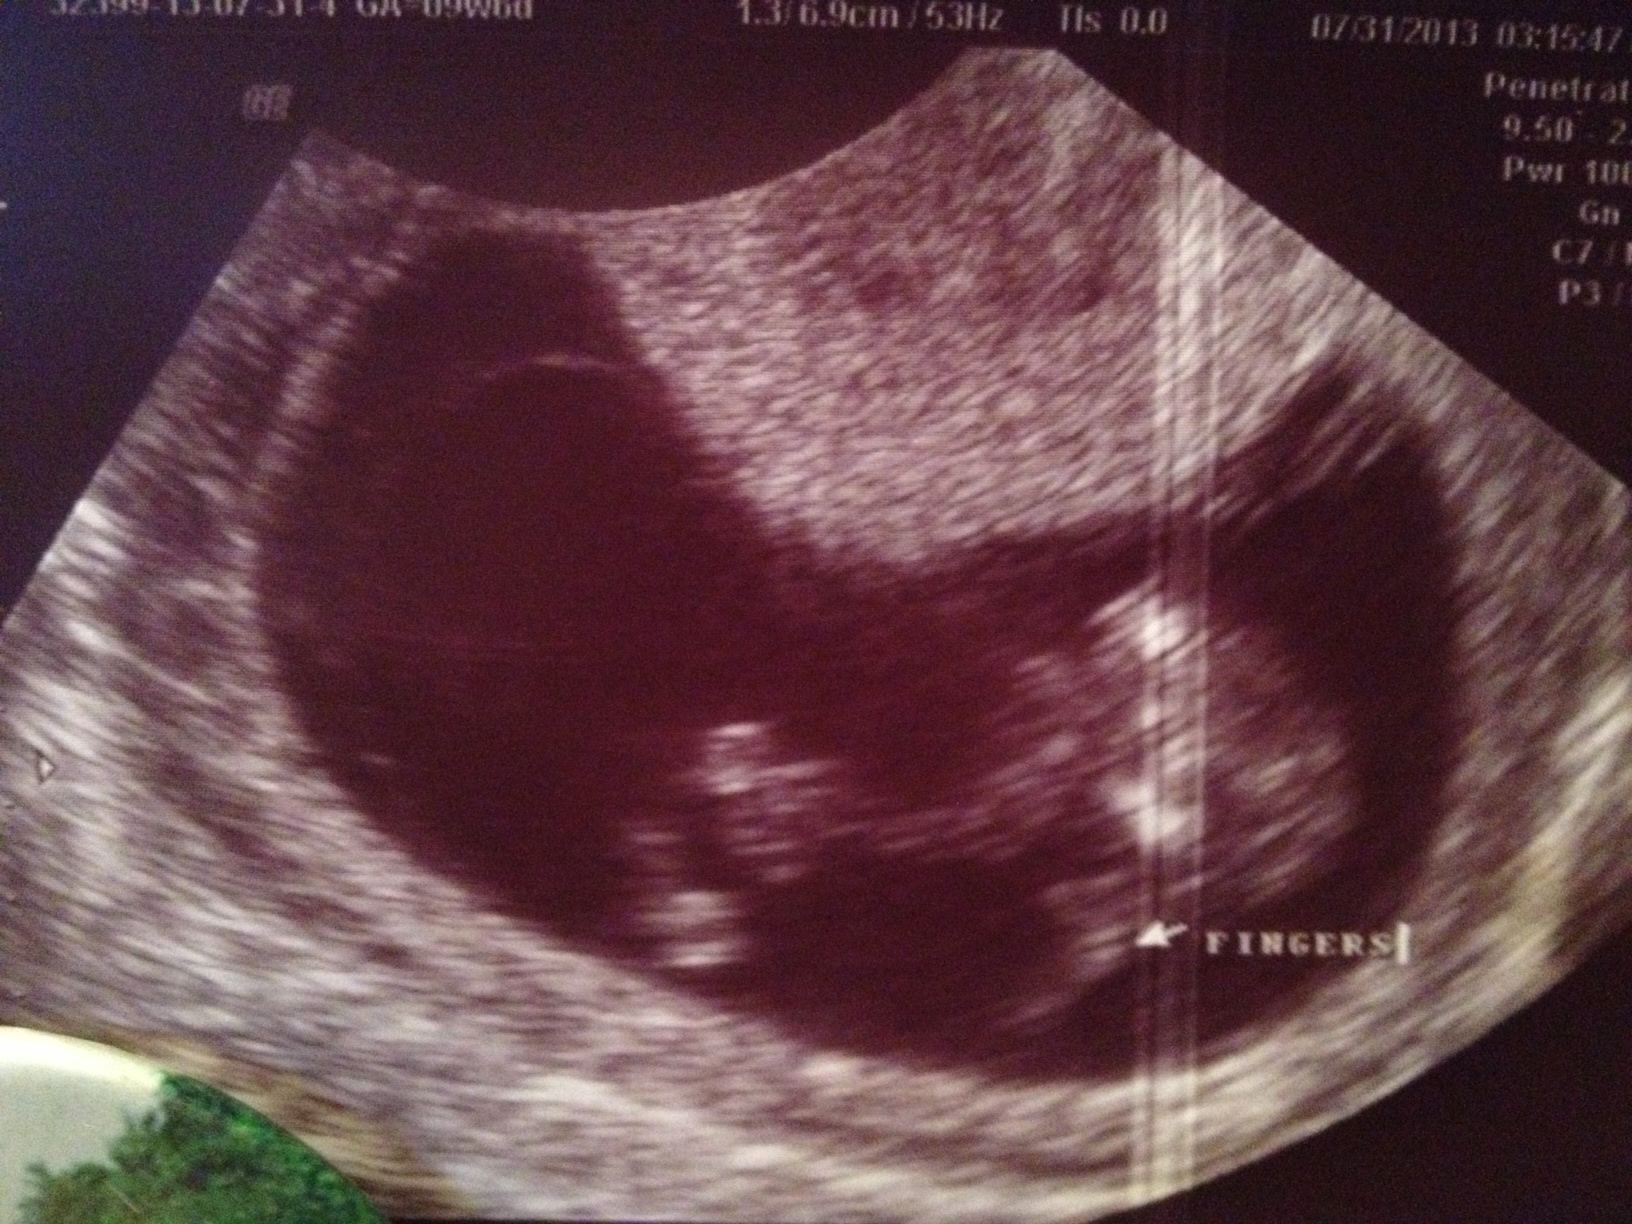

Unfortunitly I dont. This is all they gave me:( I am 10 weeks 6 days.